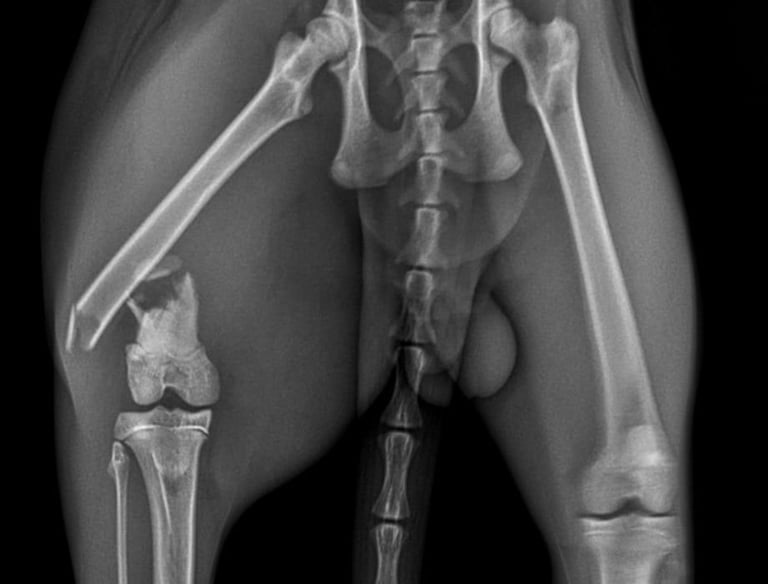

Fracturas complejas

Solución ideal para fracturas con múltiples fragmentos o alta inestabilidad.

Hueso comprometido

Indicado en pacientes con hueso débil, osteoporótico o de baja calidad.